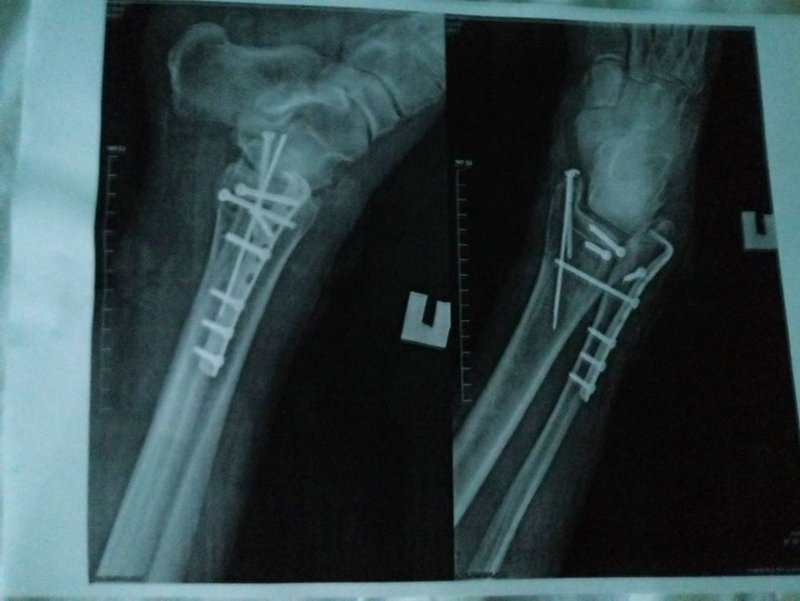

После этого одному из пассажиров Skoda Fabia водитель автомобиля MG 5 нанес несколько ударов битой по грудной клетке (результат-ушиб грудной клетки), а его напарник ногами избил второго самого физически слабого 65-ти летнего пассажира Skoda Fabia (результат-перелом ноги в трех местах). После акта превосходства над пенсионерами юные бандосики положили биту в багажник своего авто и скрылись с места происшествия, забыв третьего друга.

Фото: Сергей Барбашин